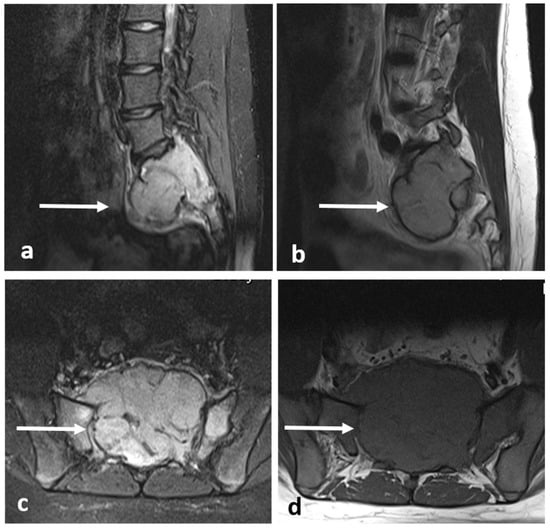

3.9. Aneurysmal Bone Cyst

| Aneurysmal bone cyst | Expansile lytic lesion with internal bone septations. | Fluid—fluid levels within the cysts, high T1 signal within layering fluid content due to haemorrhage. |